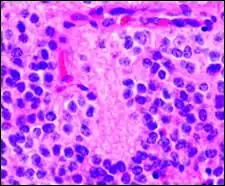

Pineocytomatous/neurocytic pseudorosettes

Histologic features of these two tumors are virtually identical, including their tendency to form neuropilrich rosettes, referred to as pineocytomatous/neurocytic rosettes in central neurocytoma. Both are quite similar to the Homer Wright rosette, but they are generally larger and more irregular in contour. The cells of the pineocytomatous/neurocytic rosettes are also considered to be much more differentiated than the cells forming Homer Wright rosettes in that the nuclei are slightly larger, more rounded, much less mitotically active, and paler or less hyperchromatic. In rare cases, these rosettes may aggregate in a sheet of back-to-back clusters resembling field stone pavement.[2]

- Micrograph of pineocytomatous/neurocytic pseudorosettes